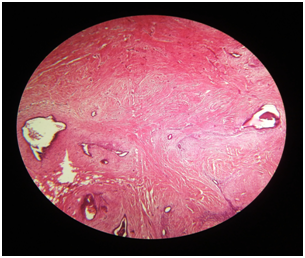

Figure 1 Photomicrograph showing benign endometrial glands and stroma surrounded by fibrous scar tissue consistent with Endometriosis (Hematoxylin and eosin x100).

Figure 2 Photomicrograph showing benign endometrial glands and stroma surrounded by fibrous scar tissue consistent with Endometriosis (Hematoxylin and eosin x200).

28 years old P2L2female patient reported to Gynecology department with a painful swelling at left angle of previous LSCS pfannenstiel scar for 6 years. She delivered her first Full term Alive and Healthy baby by LSCS 6 years back. She first felt pain at operated site 3 months after the surgery. It was cyclic and used to subside without any treatment. About 3 years back, she again conceived and delivered Full term, Alive and Healthy baby by LSCS. Now she presents with a tender swelling measuring 4x3x2cm at left angle of healed pfannenstiel scar. It was well circumscribed, firm and situated in subcutaneous plane. Rest of her systemic examination, vital parameters, laboratory investigations and sonographic examination were unremarkable without any evidence of pelvic endometriosios (Figure 1). Ultrasonogram (USG) of swelling showed well defined lesion measuring 2.6x1.5.x.15cm in left pelvic region at the pfannenstiel scar site which was predominantly hypoechoic with areas of hyeprechogenecity within. Based on USG findings along with clinical history, a diagnosis of Scar endomerisois was made. Patient was taken up for wide local excision of swelling with surrounding margins of 1 cm. Gross examination of excised tissue revealed irregular, grayish black fibro fatty mass with areas of congestion and hemorrhage. Histopathology examination revealed endometrial glands surrounded by endometrial stroma, embedded in fibro collagenous tissue and hemosiderin pigment at places without any evidence of malignancy (Figure 2). All histopathology findings were consistent with Scar endometriosis. On follow up period for 6 months, she did not report for any recurrence of swelling and was completely relived of her cyclic symptoms.